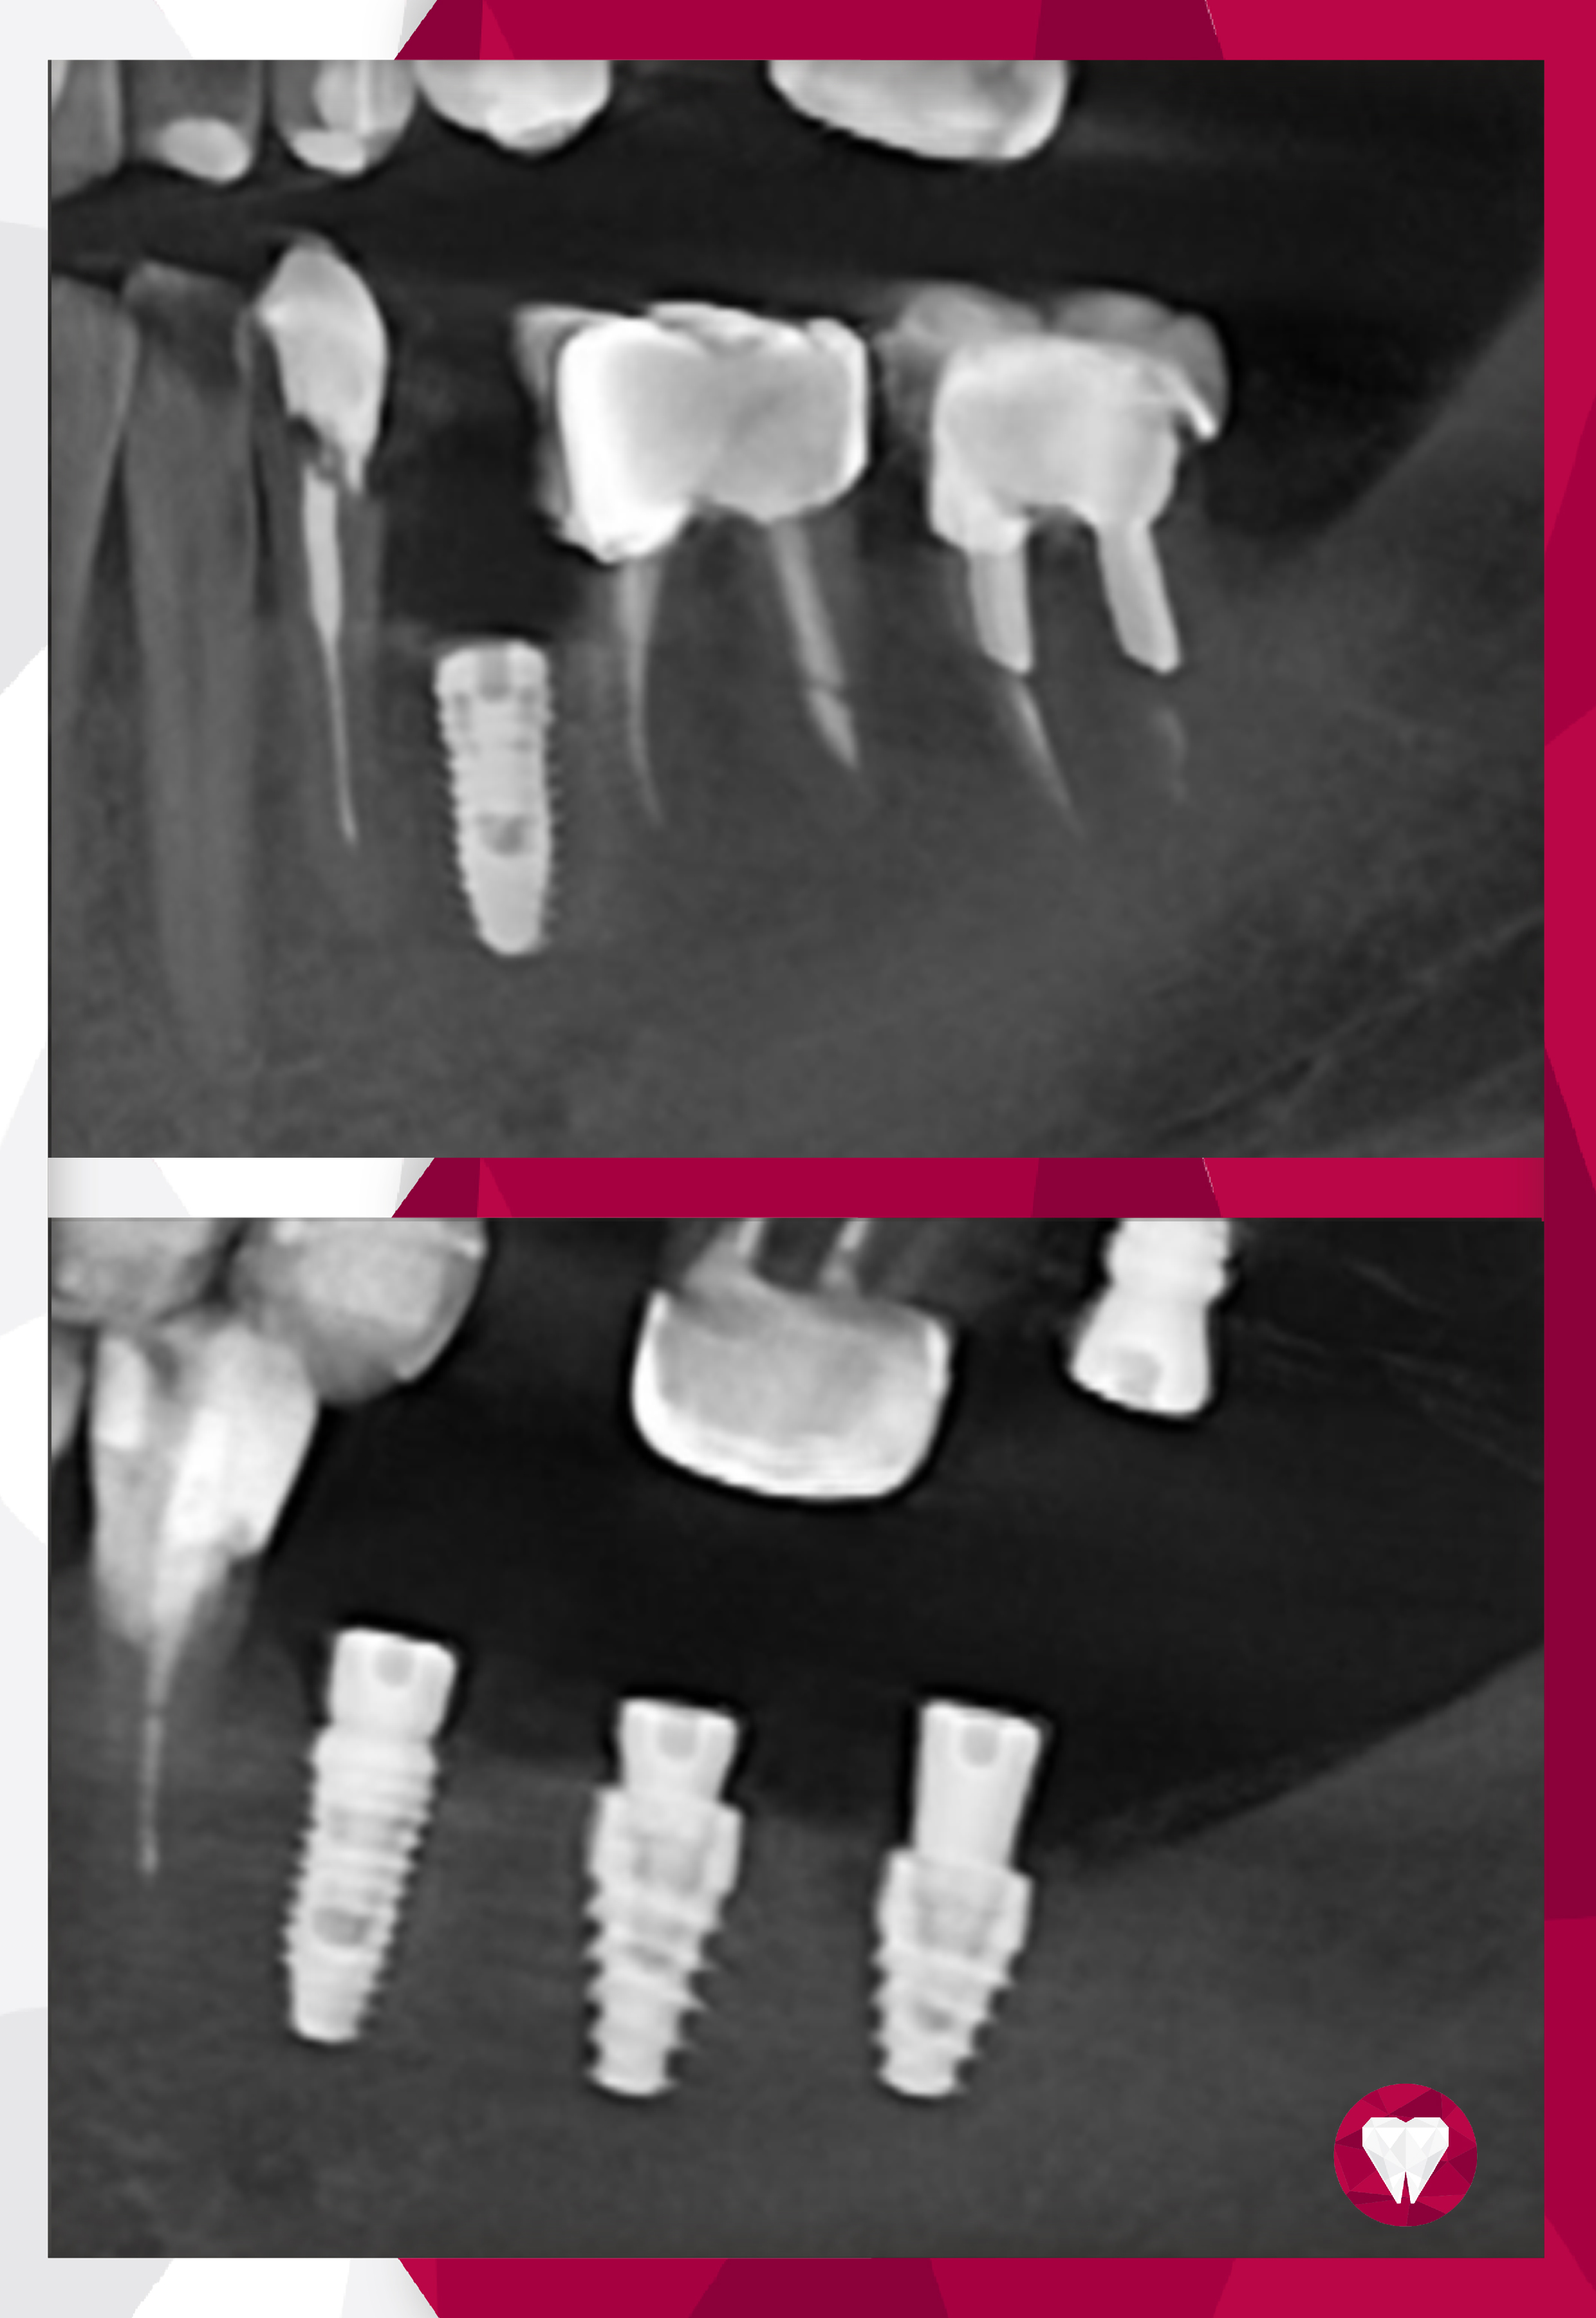

- • хирургическая установка зубных имплантов;

- • протезирование на имплантах.